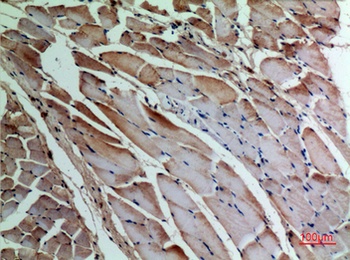

α-SMA Polyclonal Antibody

Catalog Number: orb1411650

| Catalog Number | orb1411650 |

|---|---|

| Category | Antibodies |

| Description | Rabbit polyclonal antibody to α-SMA. |

| Clonality | Polyclonal |

| Species/Host | Rabbit |

| Conjugation | Unconjugated |

| Reactivity | Human, Mouse, Rat |

| UniProt ID | P68133 |

| Tested applications | IHC-P, WB |

| Dilution range | WB: Western Blot: 1/500 - 1/2000. IHC-p: 1:100-300 ELISA: 1/20000. Not yet tested in other applications. |

| Storage | Maintain refrigerated at 2-8°C for up to 2 weeks. For long term storage store at -20°C in small aliquots to prevent freeze-thaw cycles |

| Alternative names | ACTA1; ACTA; Actin, alpha skeletal muscle; Alpha-a Read more... |

| Note | For research use only |